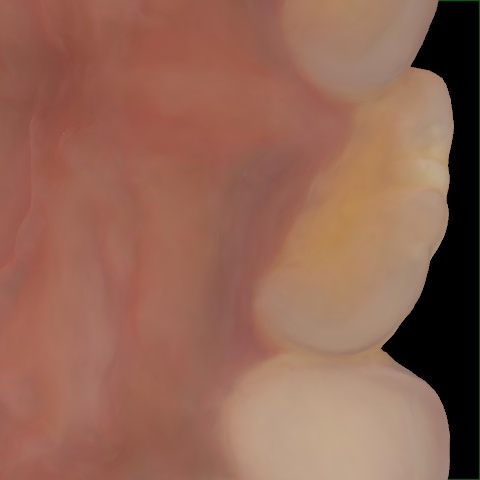

Incorrect Quality Level

The reference annotation for this image is

None

.

Please select the correct quality level.

Annotated as "Good"